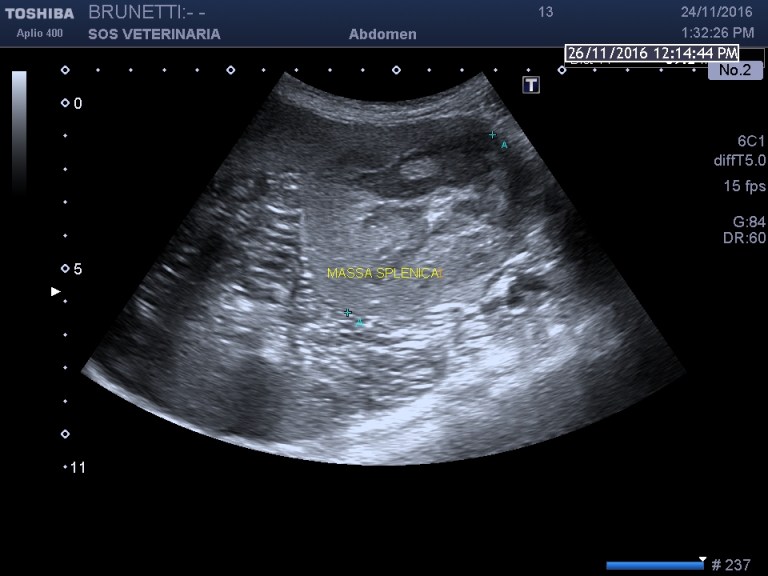

Esame ecografico

massa (circa 6 cm) situata caudalmente verso la coda dell organo eterogena nelle porzioni centrali ,omogena e simile al parenchima sano alla periferia , ben demarcata ,interrompe bruscamente il profilo dell organo,segnali colore doppler moderati non distribuiti omogeneamente e uniformemente